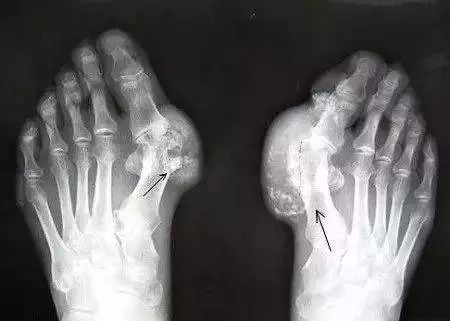

2、痛风性关节炎

痛风性关节炎主要表现为关节局部明显的红、肿、热、痛。患者关节畸形及功能障碍逐渐加重,痛风石数量增多体积增大,同时还会有患处破溃等症。一旦造成关节畸形那么,将严重影响正常的学习工作和生活。如果患者患病部位伤口长期不愈,甚至只能选择截肢以避免全身感染。